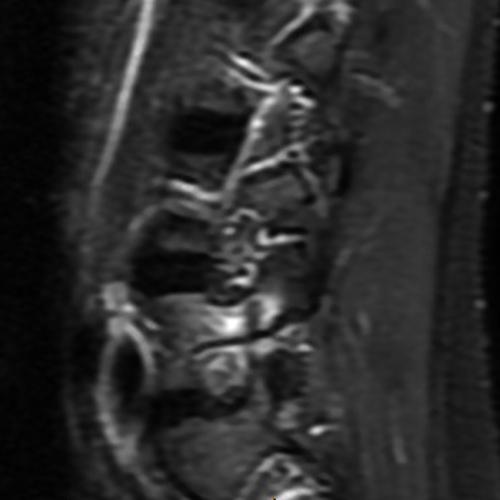

Case 1: 14-year-old female with back pain after a car accident. Axial T2-weighted (1A) and sagittal STIR (1B) images are provided. What are the findings? What is your diagnosis?

Case 1: T2-weighted axial (3A) and sagittal STIR (3B) sequences show marked cortical T2/STIR hyperintensity in the left pedicle of L5 surrounding a hypointense line (arrows) which begins at the inferior/medial margin of the pedicle and nearly completely traverses the pedicle.

Case 1: Acute left-sided pediculolysis